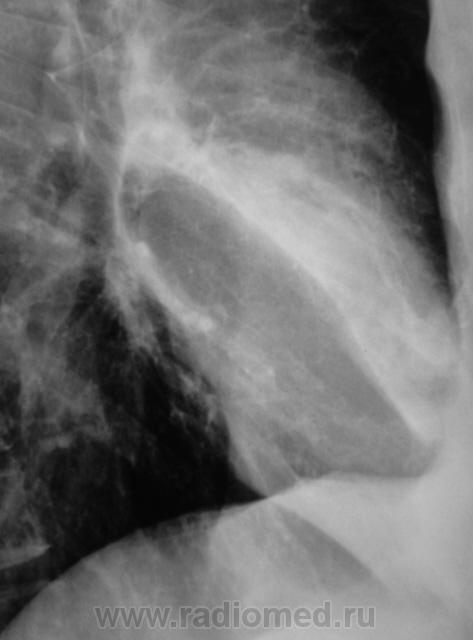

Распад был изначально, но, к счастью больного, все закончилось практическим выздоровлением.

Долго что-то пневмонию лечили. А распад очень сомнительный. Больше на игру теней похож.

Да, лечение весьма затянулось.